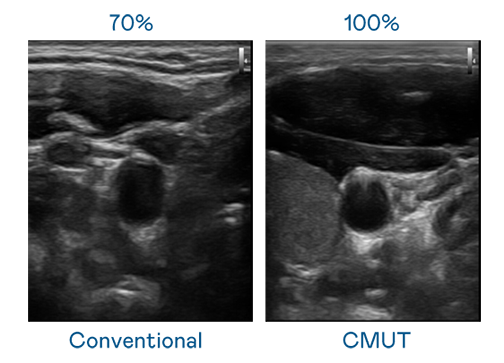

CMUT 技术是一种用电容式微机电元件来产生超音波讯号的技术。与传统 PZT 压电式技术相比,CMUT 频宽增加 30%,更宽频的超音波讯号让影像解析度大幅提升,是实现高影像品质医疗超音波扫描、促进精准医疗发展的关键技术。

大频宽带来超清晰影像

超音波影像的解析度高低,首先取决于探头能发出的讯号频宽。EBpay CMUT 可提供高清晰的超音波讯号,提供高频宽、高灵敏度、影像纹理细节更高的超音波影像,协助医护人员缩短影像判读时间及利用精准的医疗影像进行诊断。